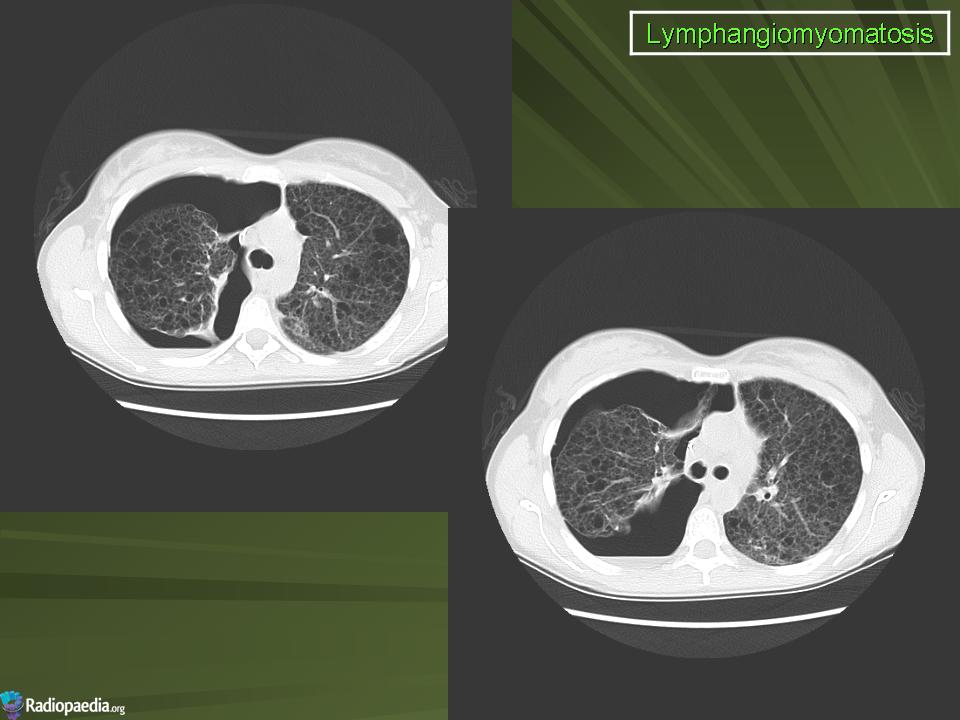

лимфангиолейомиоматоз

Типичный пример патологии при которой основным патерном являются кисты - :

Лимфангиомиоматоз.